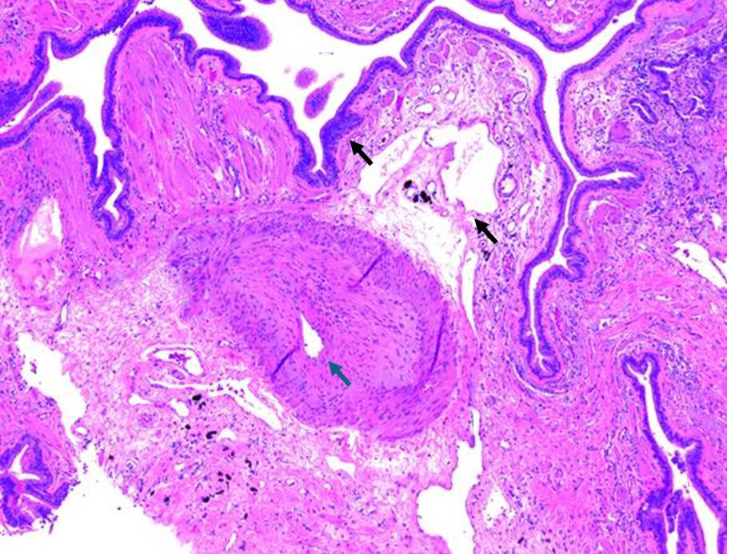

图2 ILD-PH患者的肺组织病理学显微照片

注:切片呈现出明显的肺组织结构扭曲以及上皮细胞化生增生变化(黑色箭头所示)。还可见肺动脉,其中膜和内膜明显增厚,管腔变窄(蓝色箭头所示)。